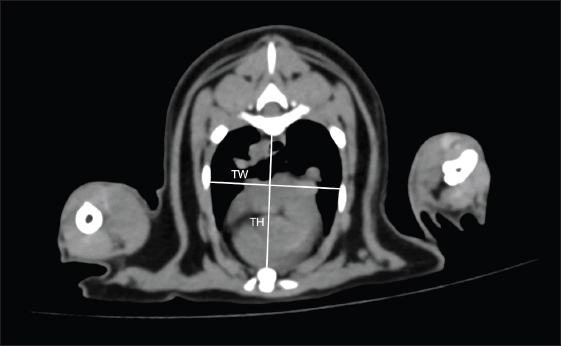

On cross-sectional images at the carina level, thoracic height/width ratio (THW) was determined as described previously (Uehara et al., 2009). A manual drawing using a digital caliper from the ventral border of the vertebrae to the sternum was performed to identify the thoracic height (TH). For the thoracic width (TW), a digital caliper was used from the right to left thoracic wall at the widest part and perpendicular to the TH as shown in Figure 2. THW was then calculated. Relative heart area (RHA) was evaluated by manually drawing the outline of the heart to evaluate the heart area (Fig. 3A). For the thoracic area (Fig. 3B), manual drawing was performed as described previously (Uehara et al., 2009). Finally, RHA was then calculated as the ratio of heart area to thoracic area at the carina level. Transverse vertebral heart score (tVHS) was determined by manual drawing using a digital caliper. Heart height (HH) was the height of the heart and heart width (HW) was the widest distance perpendicular to the HH. The ratio of the sum of HH and HW to the height of the vertebral body at the carina level was then calculated as tVHS (Fig. 4). CT vertebral heart score (ctVHS) was evaluated on the sagittal plane images. The measurement method was performed in the same way as on radiography (Lister and Buchanan, 2000) (Fig. 5). All CT measurements were performed by the same experienced radiologist using the same image archiving PACs system through DICOM viewer software.

Fig. 2. THW measurement methods. THW was measured on cross-sectional CT image at the carina level. TH was distance from ventral border of the vertebrae to the sternum. TW was distance from the right to left thoracic wall at the widest part and perpendicular to TH. THW: thoracic height/width ratio; CT: computed tomography; TH: thoracic height; TW: thoracic width.